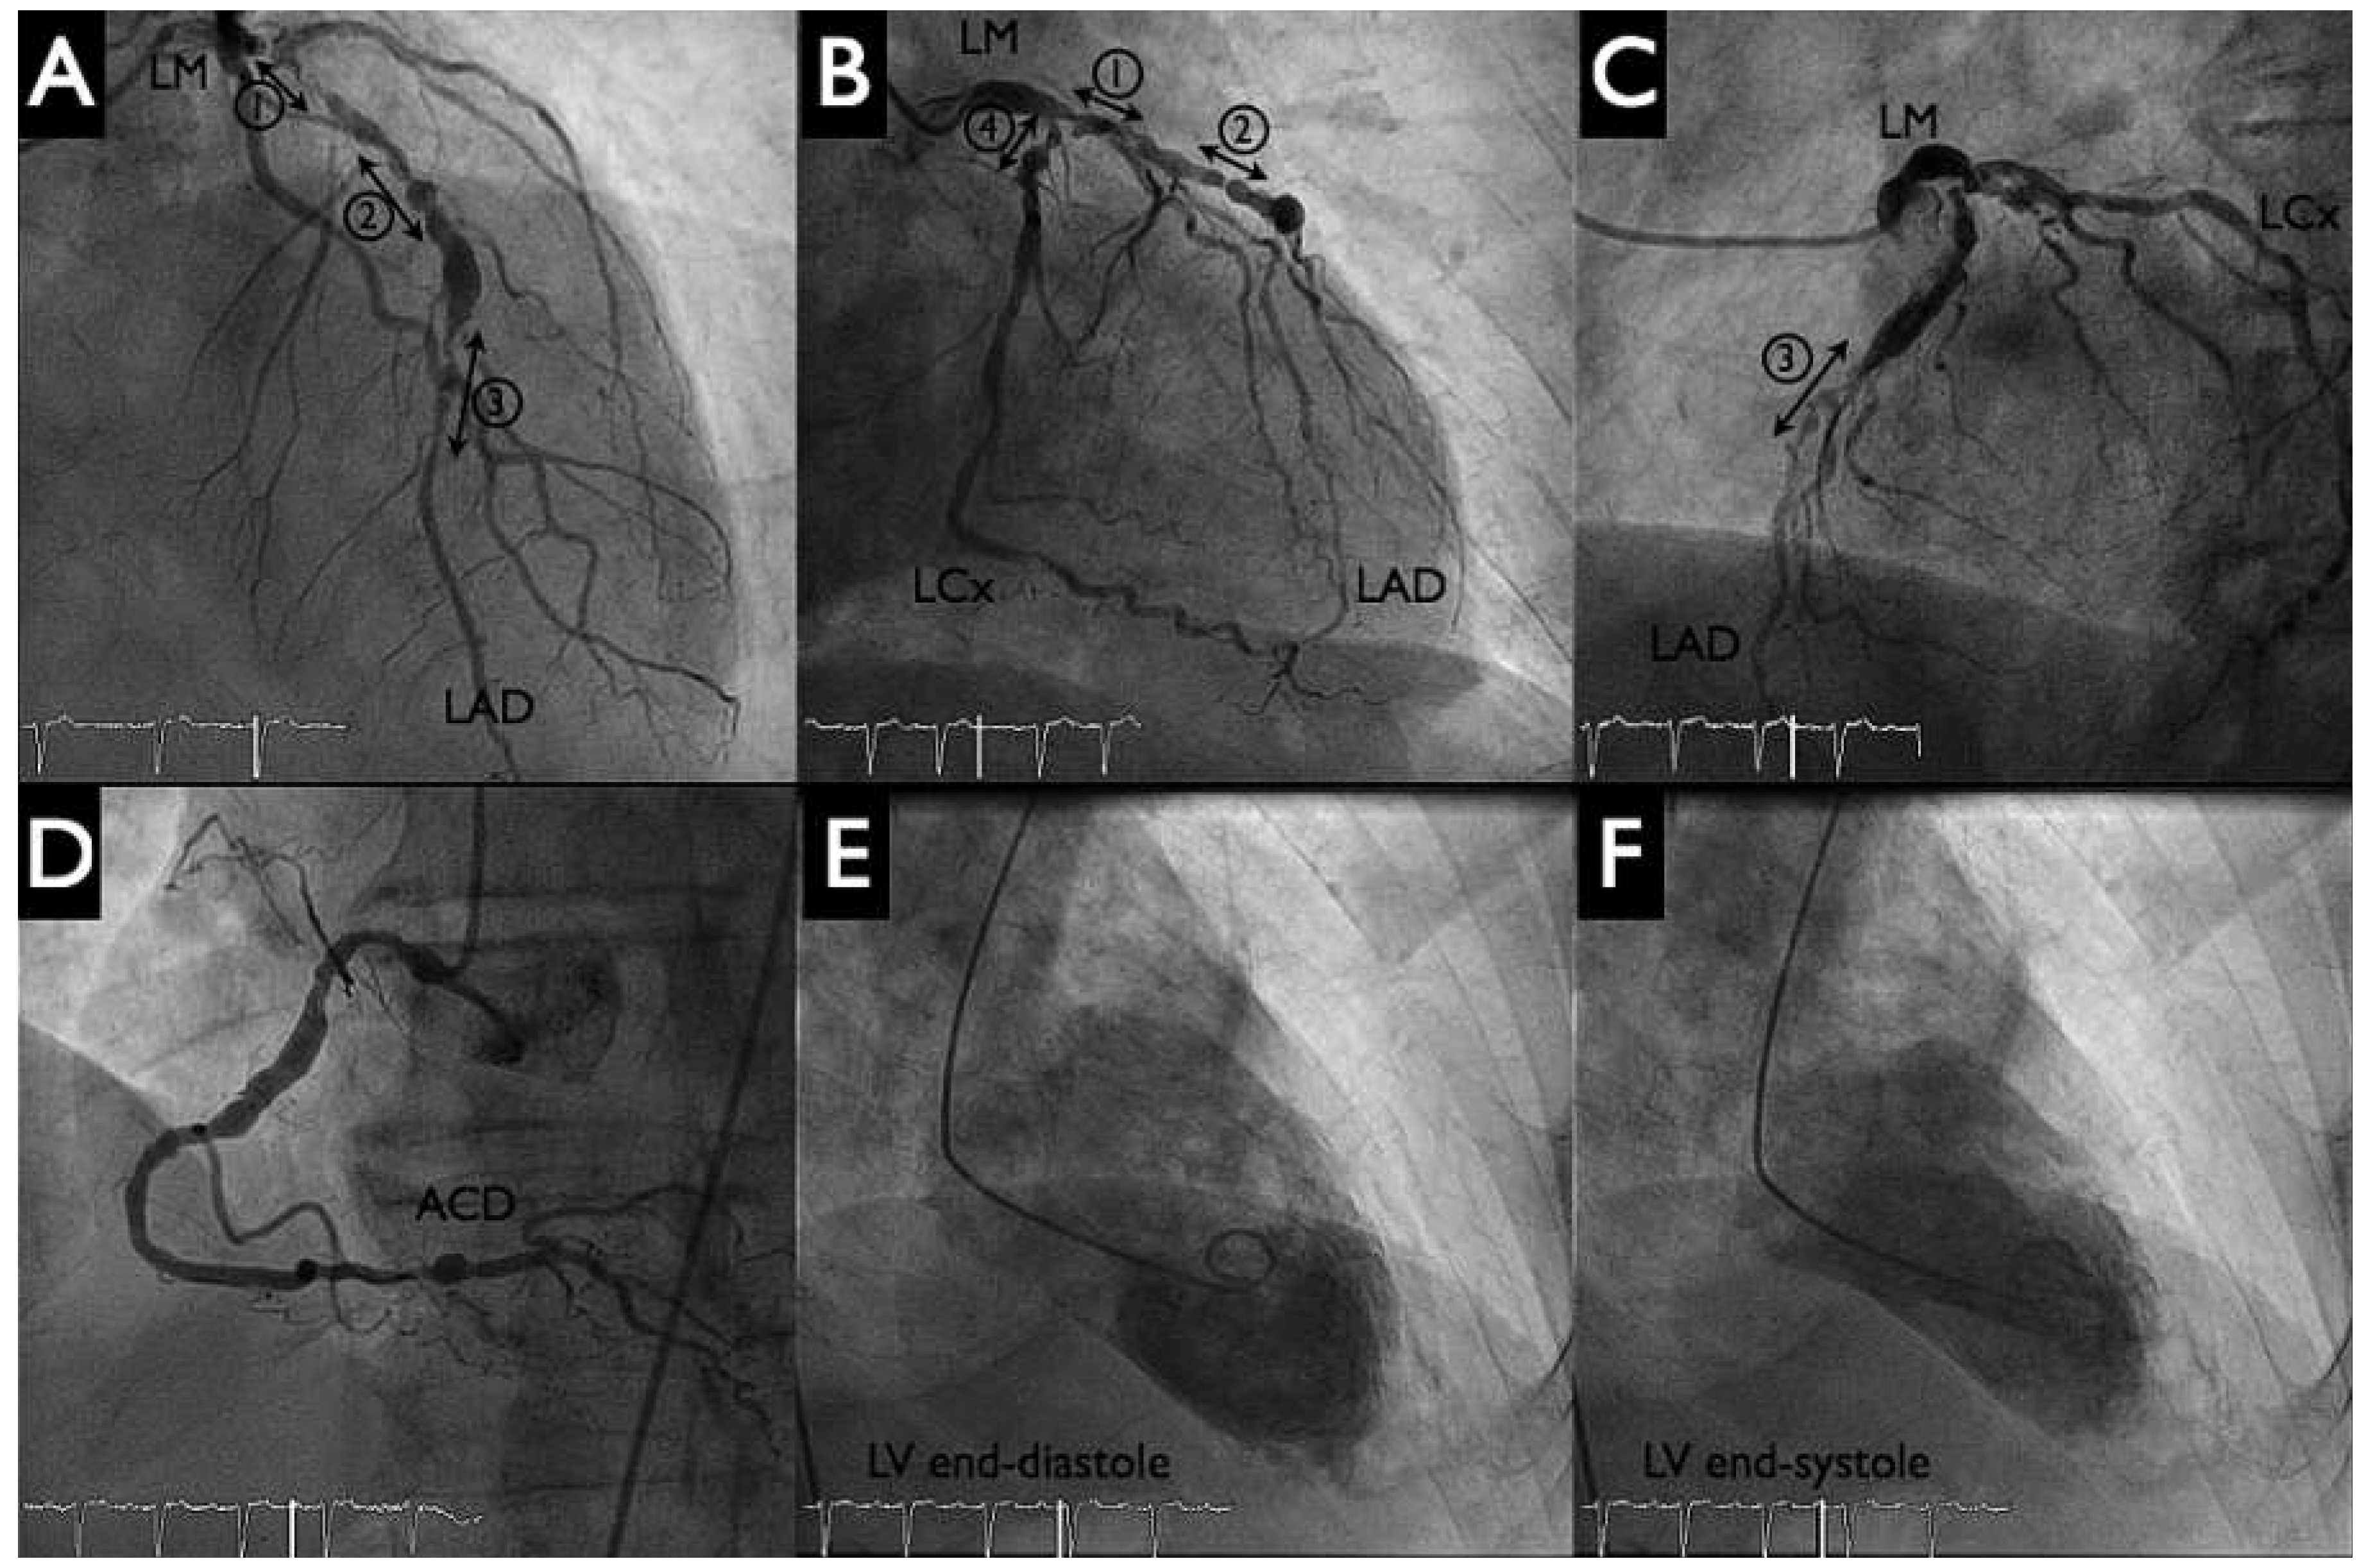

Figure 3. HeartMate-PHP implantation. Panel A: puncture of the left femoral artery under fluoroscopy. Panels B, C: Deployment of the HeartMate conduit by pulling out the covering sheath. Dashed line delineates the aortic valve.

After the patient had given written informed consent, the decision to perform a HeartMate-PHP-assisted PCI was made. Both groins were used for vascular access. Following local anaesthesia, puncture of the left femoral artery under fluoroscopy (Figure 3 panel A) and preclosure of the left femoral with two Perclose devices were performed. Then, a 14 French (Fr) sheath was placed into the descending aorta. Systemic anticoagulation was achieved with administration of unfractionated heparin (70 U/kg); the patient had been pretreated with acetylsalicylic acid 100 mg/day. A 5 Fr JR4 catheter was positioned in the left ventricle and then exchanged over a 0.018 inch guidewire for the HeartMate-PHP catheter. The correct position of the device was verified by fluoroscopy by using a 5 Fr pigtail catheter from the right femoral artery as a marker of the aortic valve and the conduit was unsheathed up to its final 24 Fr size (Figure 3 panels B, C). Circulatory support was initiated at the minimum pump speed (approximately 1 l/min) and maintained throughout the intervention. Activated clotting time was kept at 250 s.